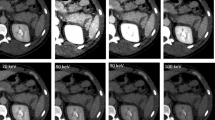

CT studies were performed on a Brilliance 16-MDCT scanner (Philips Medical Systems, Best, The Netherlands), with intravenous injection of 120 ml nonionic iodinated contrast material [Iomeron (iomeprol), 300 mg I/ml, Bracco] at a rate of 3–4 ml/s using a power injector. The CT scan was acquired with detector collimation of 16 × 0.75 mm and slice thickness reconstruction of 3 mm with 1.5 cm overlap. CT angiography studies were done to rule out arterial injury with detector collimation of 16 × 0.75 mm and slice thickness reconstruction of 2 mm with 1 cm overlap. No oral contrast was administered.

Technique—an isotropic dataset

As prerequisite for diagnostically acceptable MPRs, a CT study should be acquired in an isotropic manner, meaning that an image voxel has equal and sufficiently small width, height, and depth [15–17], thus producing MPR images without artifacts. In our hospital, at the time of the second Israel–Lebanon war, we had a 16-slice CT. Trauma studies were acquired with the above-described technique, which produced voxel size of 1.5 × 0.78 × 0.78 mm for regular trauma studies and voxel size of 1 × 0.78 × 0.78 mm for CT angiography studies. Even though both datasets are not fully isotropic, we have found that it was possible to produce diagnostic MPRs with minimal artifact. With the widely available 64-slice CT machines, acquiring isotropic data is a routine, thus allowing better performance with MPR.